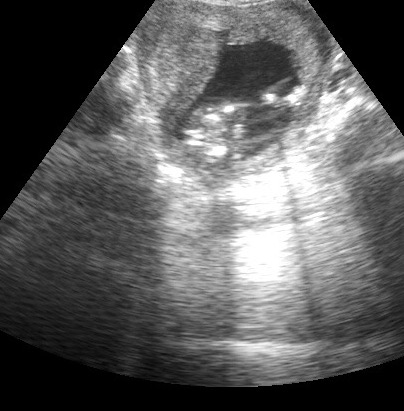

but now i saw this on the scan! (Second pic)

17 weeksAttachment 35946